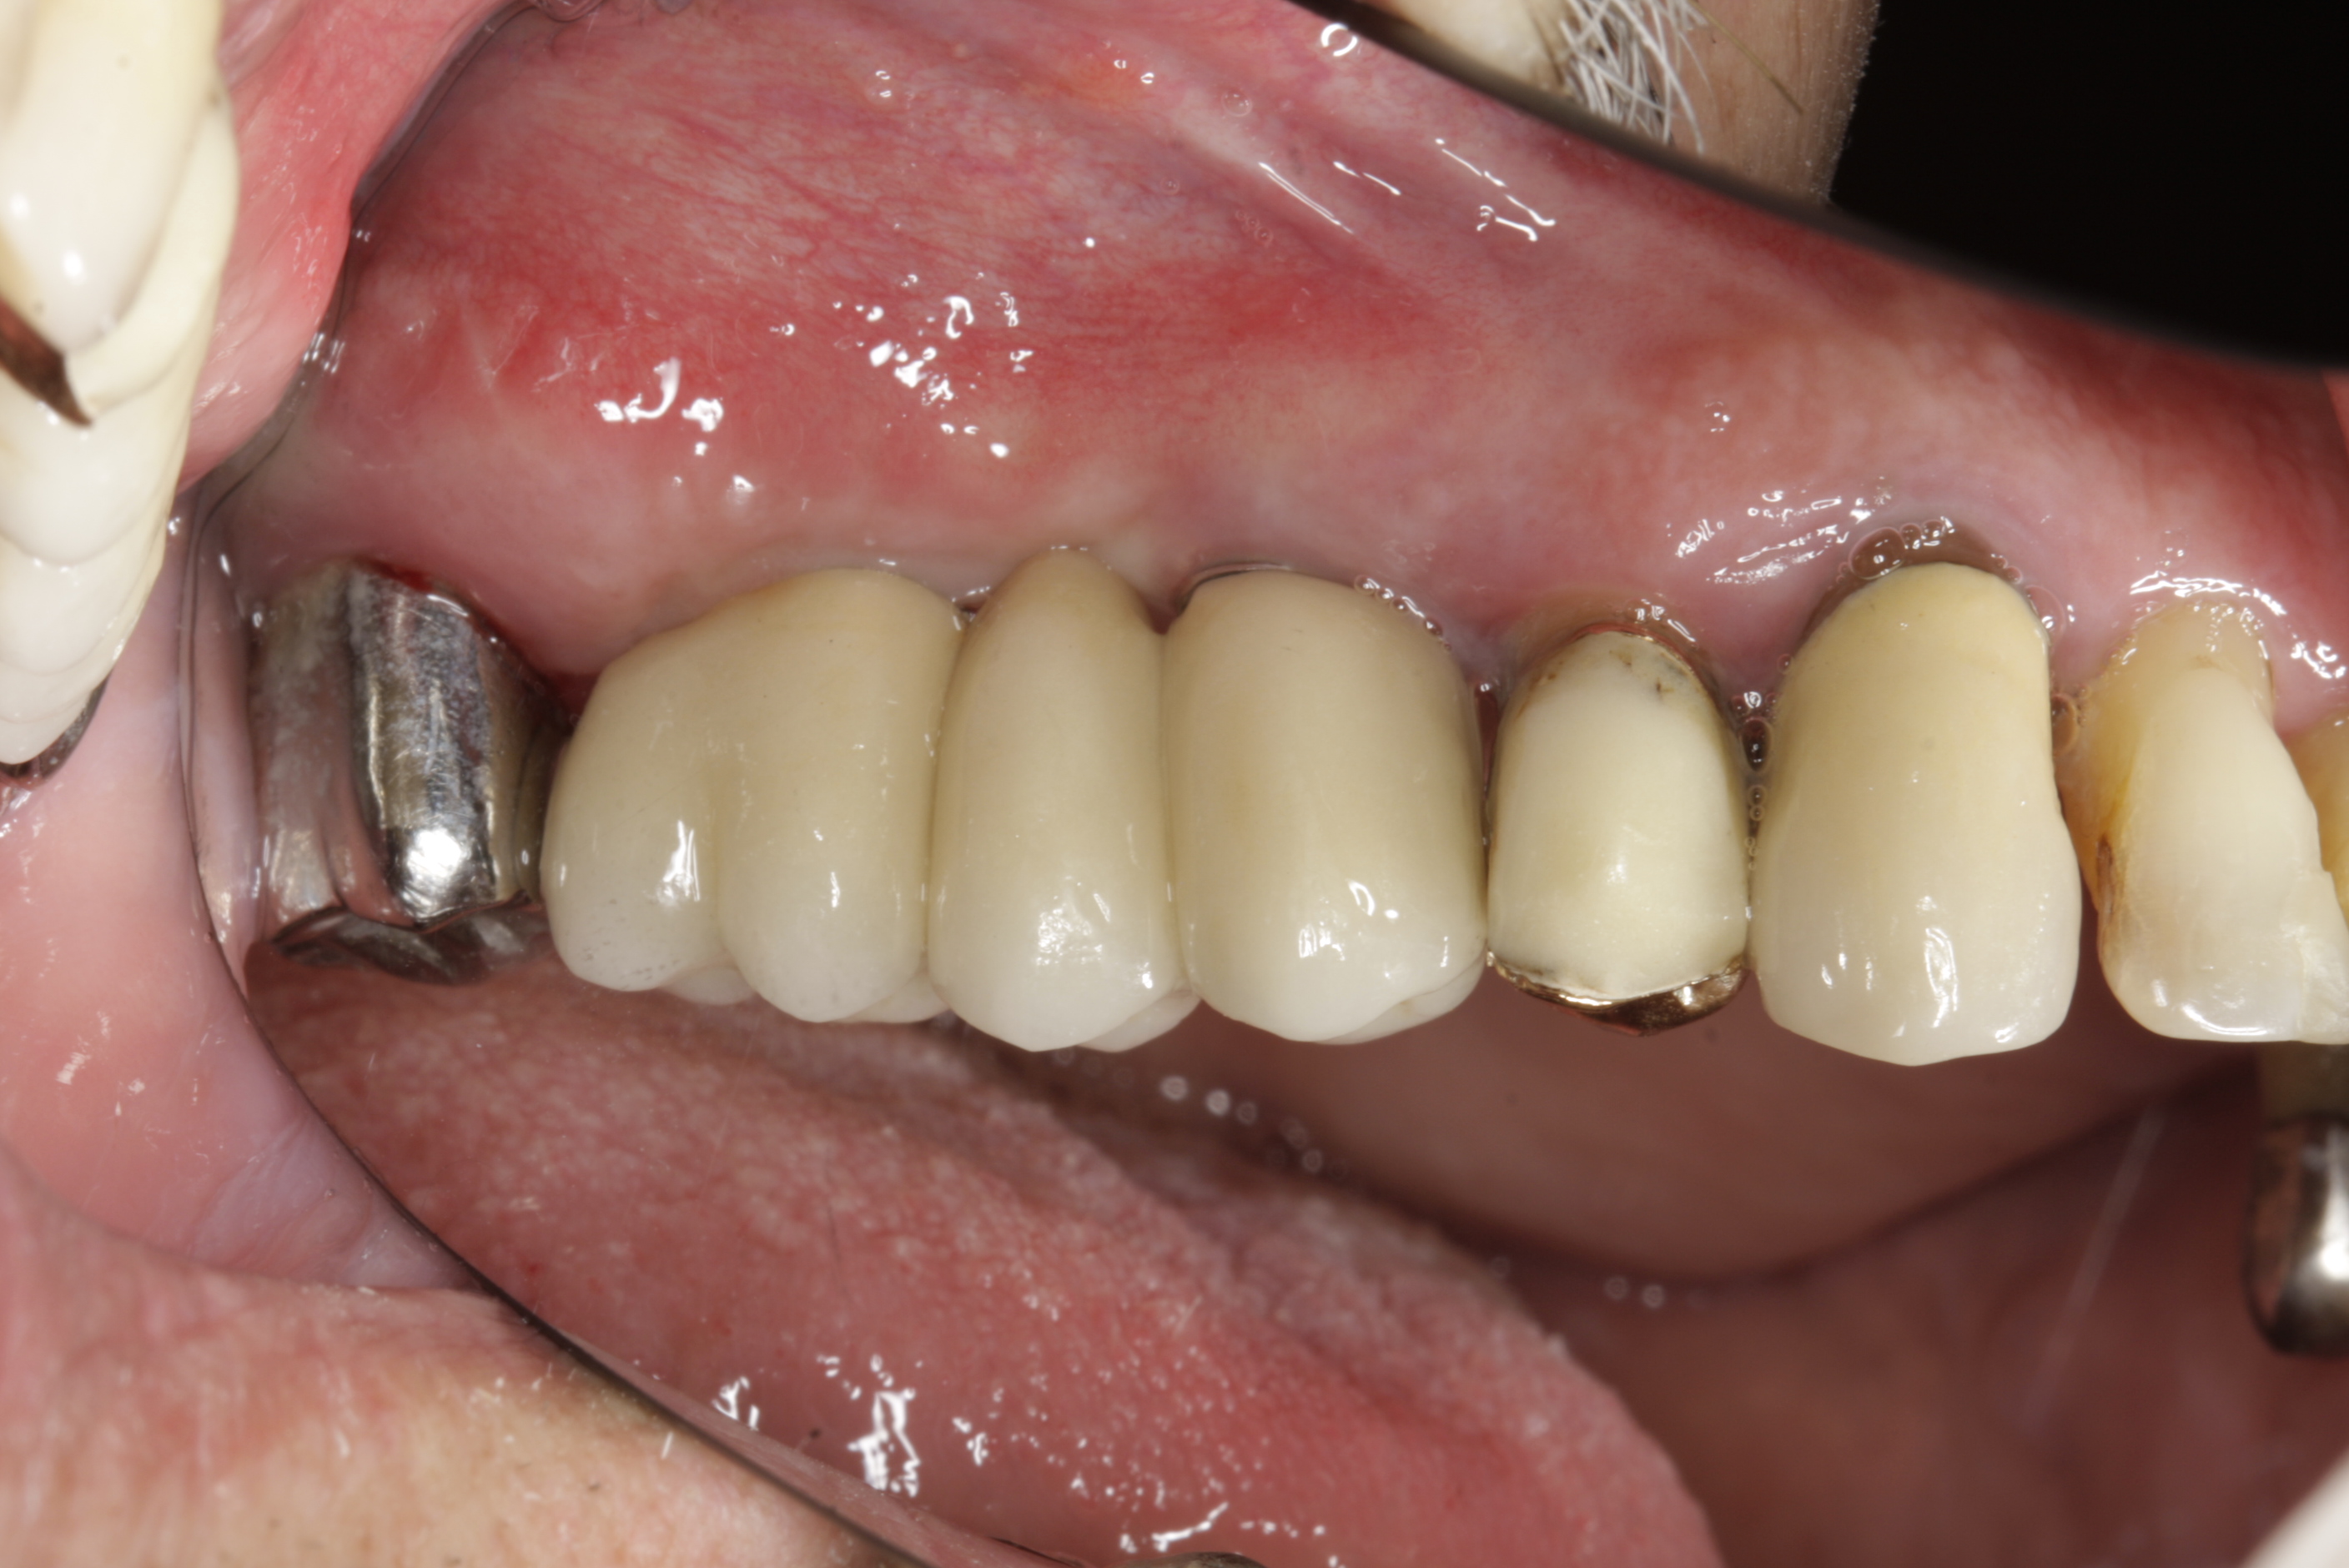

V případě chybění většího počtu zubů v postranních úsecích čelistí je možné ošetření pomocí implantátů, které nahradí ošetření pomocí snímacích náhrad kotvených na zbývajících zubech nebo patře.

Podmínkou je opět dostatečné množství kosti.

Protetické řešení může být pomocí můstku, který je kotvený na implantátech nebo pomocí jednotlivých korunek na implantátech.

V zásadě je možné do těchto můstků zařadit i přirozené zuby, zejména pokud je potřeba tyto zuby ošetřit proteticky – korunkami. Korunky nebo můstky mohou být na implantáty nacementovány nebo přišroubovány.

Zdravé zuby zůstanou zachovány a přitom náhrady jsou pevné, jako na vlastních zubech